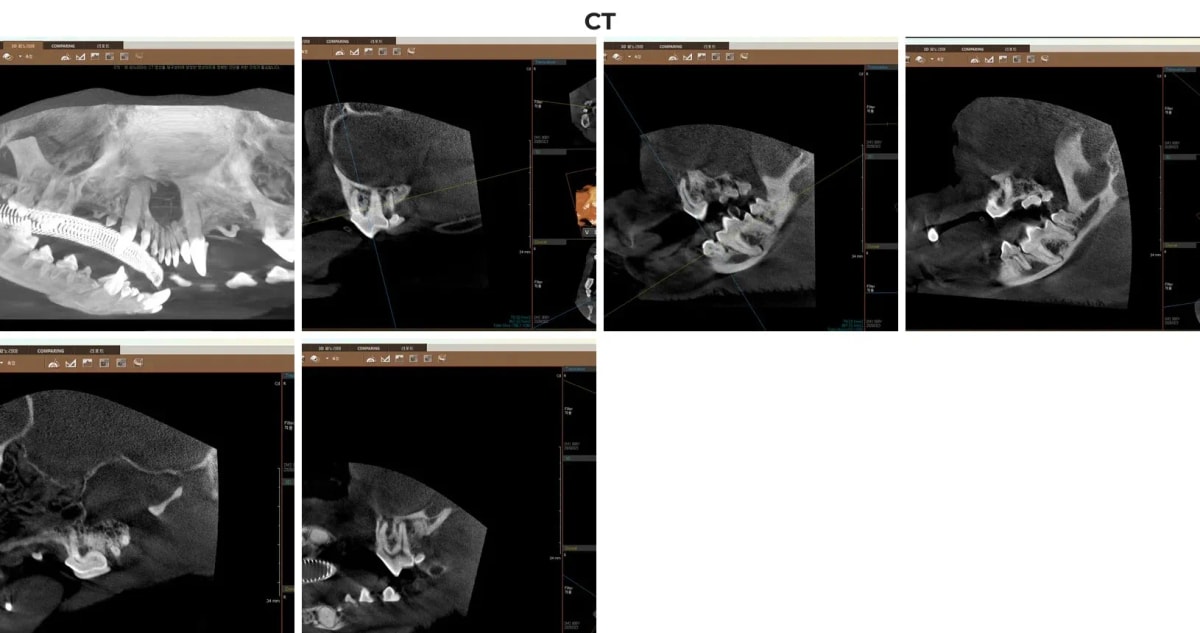

ℹ️ 치과 CT의 중요성

일반 구강 방사선(X-ray)만으로는 2차원적인 그림자만 볼 수 있어 치아 뿌리의 복잡한 구조나 상악골 내부의 미세한 염증(치근단 농양)을 놓칠 수 있습니다. 광주 전남 유일 치과 CT를 통해 3차원 입체 영상으로 치조골의 파괴 정도와 주변 신경, 혈관과의 거리를 밀리미터 단위로 파악함으로써, 가장 안전하고 오차 없는 수술 계획을 수립할 수 있습니다.

크롱이의 치과 전용 CT 스캔 이미지 (치근단 농양 확인)

치과 CT 촬영 결과, 우측 상악 제4소구치(108번 치아) 뿌리 주변으로 심각한 고름 주머니(PA3 단계의 치근단 병변)가 확인되었습니다. 이 부위는 아이가 음식을 씹을 때마다 극심한 통증을 유발하는 핵심 원인이었습니다.